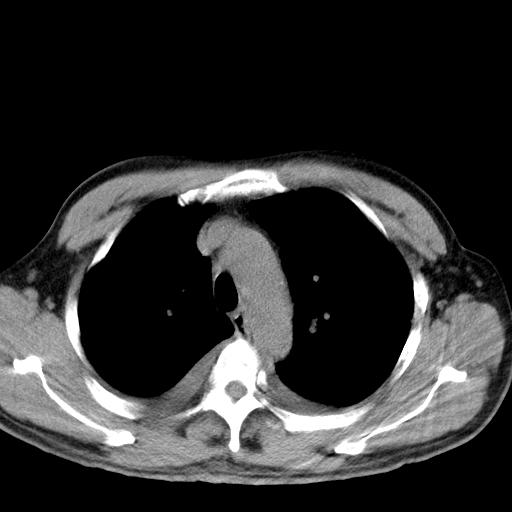

以下是引用zjzjr在2010-3-21 17:39:00的发言:[br]右下中心型肺癌并阻塞性肺炎/不张,纵膈淋巴结肿大,右侧大量胸腔积液,左侧少量胸腔积液

以下是引用zxl51642在2010-3-21 17:06:00的发言:[br]右下中心型肺癌并阻塞性肺炎/不张,纵膈淋巴结肿大,右侧大量胸腔积液,左侧少量胸腔积液,少量腹水。建议纤维支气管镜进一步检查。